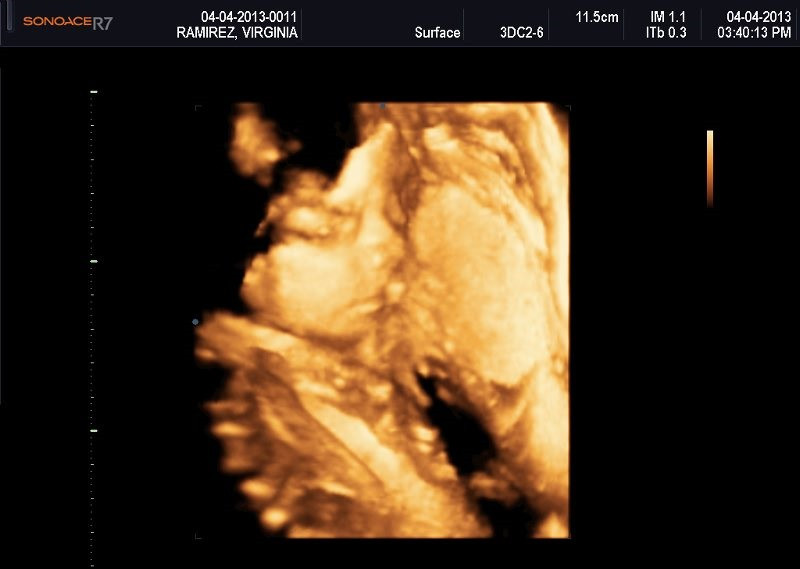

Varias ultrasonografías en 2D y 3D

Envíado por Dr. Nelson Menjívar Sarco